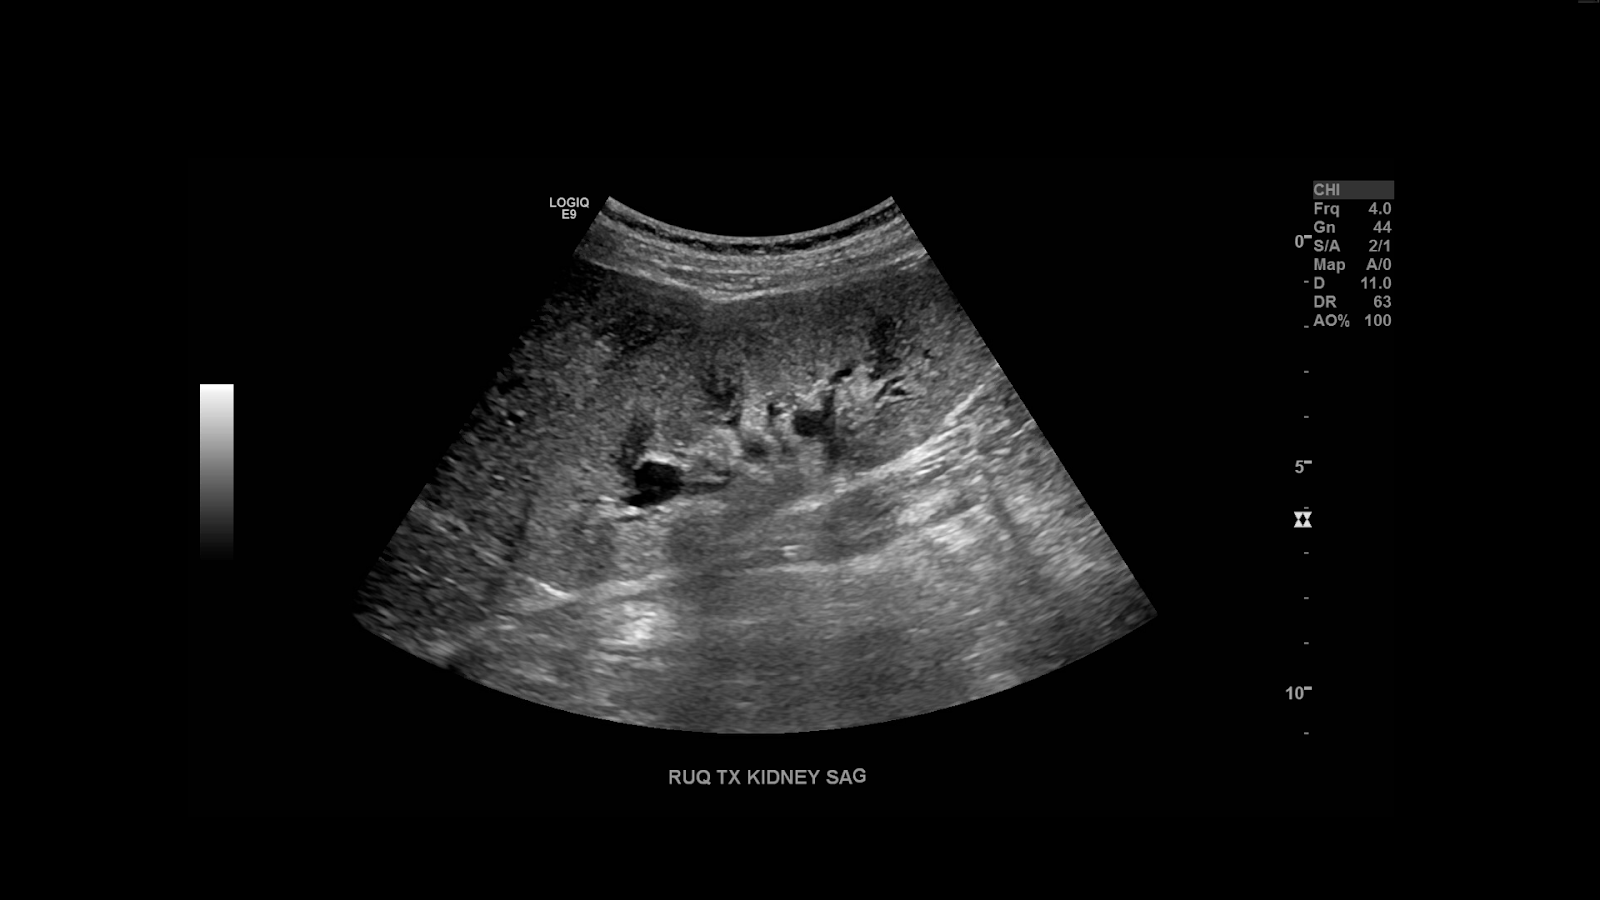

I like to begin the exam examining the native kidneys. Now a transplant recipient is likely to have suffered some chronic kidney disease, as such the native kidneys may be scarred, atrophic and in some cases imperceptible due to sever atrophy or surgery. In either case image the right and left renal fossa.